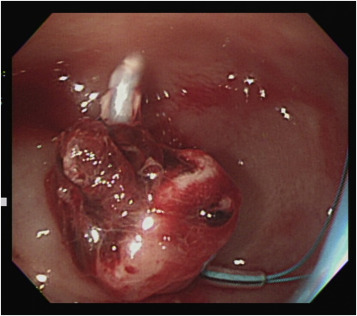

A 65-year-old man was referred to our emergency department for surgical intervention of refractory post-polypectomy hemorrhage. The patient had a medical history of hypertension, diabetes, and gout. He was not taking aspirin or other anticoagulant medication. According to the referral sheet, the polyp was 2 cm in diameter with a thick stalk in the descending colon. The referring physician had administered a prophylactic injection of diluted epinephrine into the polyp base, with two prophylactic endoclips placed before the procedure. Massive bleeding developed immediately after the procedure, and the referring physician attempted hemostasis with further injection therapy and heat-probe coagulation; however, it was not successful. The patient went into shock and was transferred to our hospital 2 h after the procedure. At the emergency department, the patient was pale and hypotensive, with a systolic blood pressure of 84 mmHg with tachycardia (heart rate: 110 beats/min). Blood test revealed a drop in hemoglobin from 14.2 g/dL to 8.9 g/dL and a normal coagulation profile. An emergent abdominal computed tomography (CT) scan revealed active contrast extravasation in the descending colon (Figure 1 , arrow), and a proctology surgeon was consulted for surgical intervention. After discussion with the patient, the patient requested a second attempt at colonoscopy to control his bleeding, and an emergent colonoscopy was performed. A large amount of fresh bloody content was found between the rectum and the descending colon. After copious irrigation with water and positional change, the bleeder source was identified (Figure 2 ).

Abdominal computed tomography span revealed active contrast extravasation from ...

Figure 1.

Abdominal computed tomography span revealed active contrast extravasation from the descending colon (arrow).